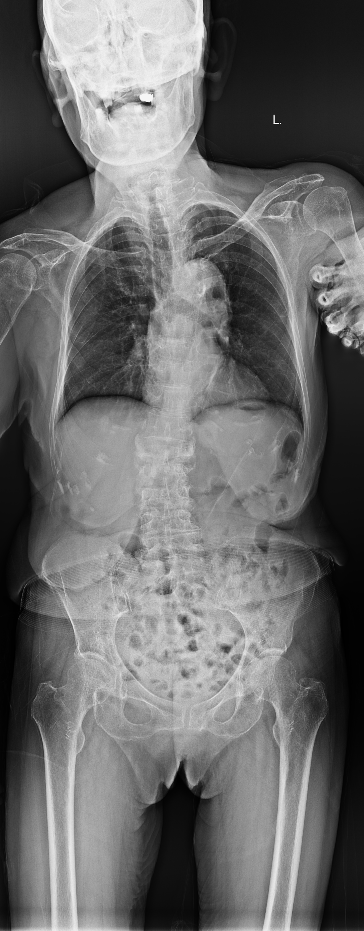

胸腰椎MRI检查结果显示:腰1椎体新近压缩性骨折伴积气,继发椎管狭窄;腰2、3椎体及腰4椎体上缘新近骨折。

影像学结果明确了患者为“骨质疏松伴多节段病理性骨折”,并伴有明显的脊柱后凸畸形和腰椎不稳。骨密度检测T值-4.25,提示重度骨质疏松。

影像学检查提示多节段脊柱病变

接诊后,科室为吴婆婆安排了详细的影像学检查,结果令人震惊。磁共振显示,她的骨折远非此前所知的一处,骨折下方的三节椎体腰2至腰4多个椎体都出现了新鲜压缩性骨折。更关键的是,最初的腰1椎体骨折并未愈合,属于“骨折不愈合”状态,并在重力作用下逐渐塌陷,导致脊柱后凸畸形(俗称“驼背”)。

术前(左)和术后(右)对比: 术后脊柱后凸矫正,骨折椎体强化固定